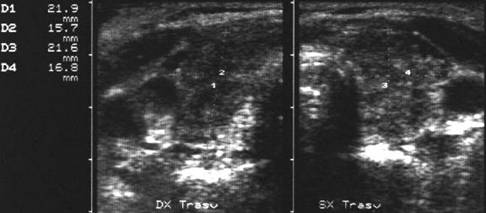

Apexul lobului drept, proiectie longitudinala si trasversala.

Femeie 58 ani. Maladia Graves in tratament cu

metimazol.

Nodul unic in apexul lobului drept, de 11x14x20mm (1,5 cc), hipoecogen, cu

contur difuz

Nu s-a efetuat citoaspiratie.

Aceeasi pacienta. La ecodoppler color - vascularizatie

periferica, avascular intralezional.

Ecopowerdoppler confirma absenta vascularizatiei interne.